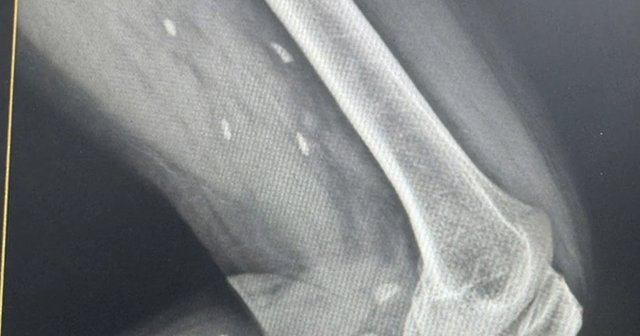

Nhiều kén sán kích thước như hạt gạo nằm rải rác ở các mô vùng xương đùi và cẳng chân bệnh nhân.

Người bệnh đến thăm khám khi có triệu chứng mệt mỏi, đau nhức nhiều ở vùng chân, lưng, hạn chế vận động… Bệnh nhân được chỉ định thực hiện chụp X- quang thường quy.

Bác sĩ Đỗ Hồng Thanh, Phó Giám đốc Trung tâm Y tế khu vực Thạch Hãn chia sẻ với Sức khỏe & Đời sống , kết quả X – quang phát hiện nhiều kén sán kích thước như hạt gạo nằm rải rác ở các mô vùng xương đùi và cẳng chân bệnh nhân.